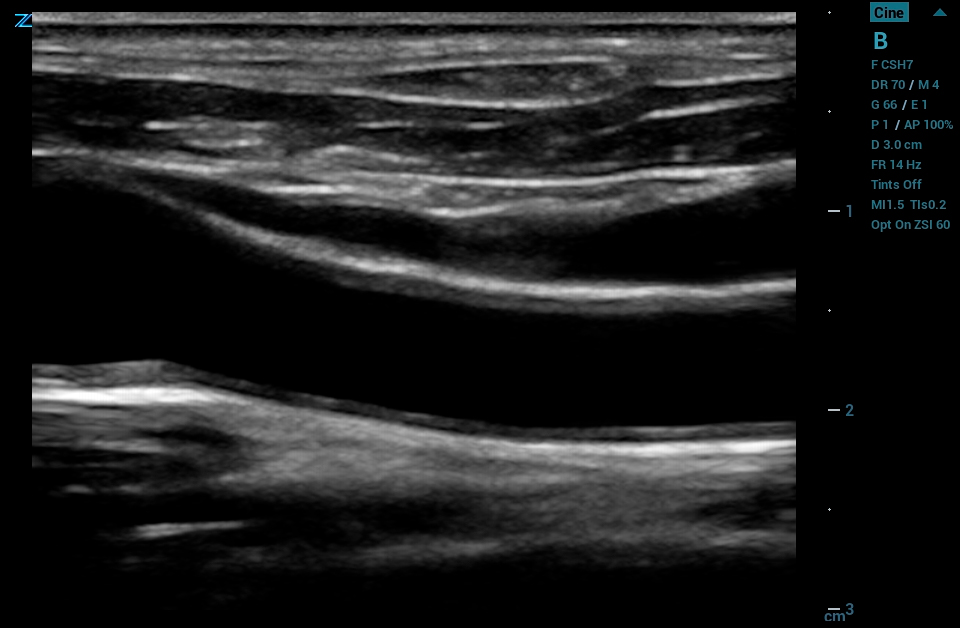

The ZS3 Ultrasound System Diamond Edition 2.0 is the ultimate imaging platform combining premium performance and mobility for today’s demanding ultrasound environments. Equipped with next generation ZONE Sonography® Technology+ (ZST+), the ZS3 System takes image clarity to new heights across a broad spectrum of body types from pediatric to bariatric. With every pixel in focus to imaging depths up to 40cm, the ZS3 System delivers unsurpassed image quality for the widest range of clinical applications.

The ZS3 Radiology Ultrasound System is a smaller, lightweight system that glides into place. An extended battery combined with rapid transition times results in increased exam efficiency and patient throughput.